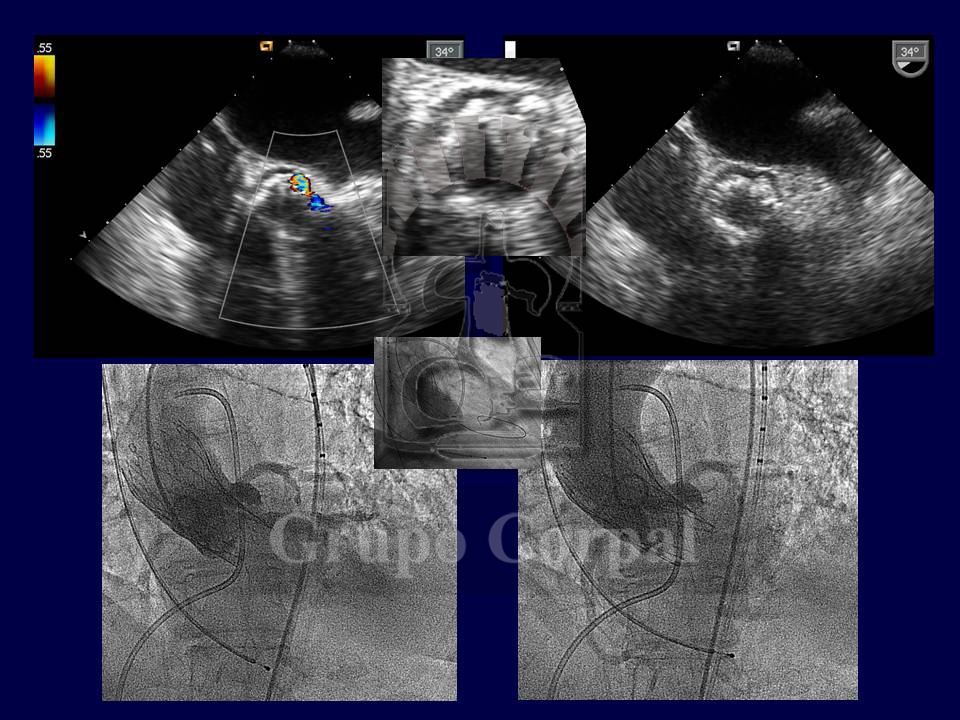

From a technical perspective, percutaneous implantation is simple and standard. It requires general anaesthesia and 2 artery (both femoral) and 2 venous punctures (1 femoral and 1 jugular). The jugular route is for the implantation of an electrode catheter in the right ventricle, which acts as a preventive pacemaker, as transient or definitive atrial-ventricular block occasionally onsets during implantation (15%). The 2 femoral artery routes help us to monitor systemic and ventricular pressure before, during and after the procedure, to evaluate the outcome. They also help us to angiographically select the appropriate puncture site to insert the cannula that carries the valve and small aortographies during implantation.

Although not essential, it is also advisable to monitor the implantation by transoesophageal ultrasound. After implantation, the outcome is evaluated both haemodynamically and angiographically and the point of insertion is closed by a Prostar device, verifying the outcome by contralateral angiography.